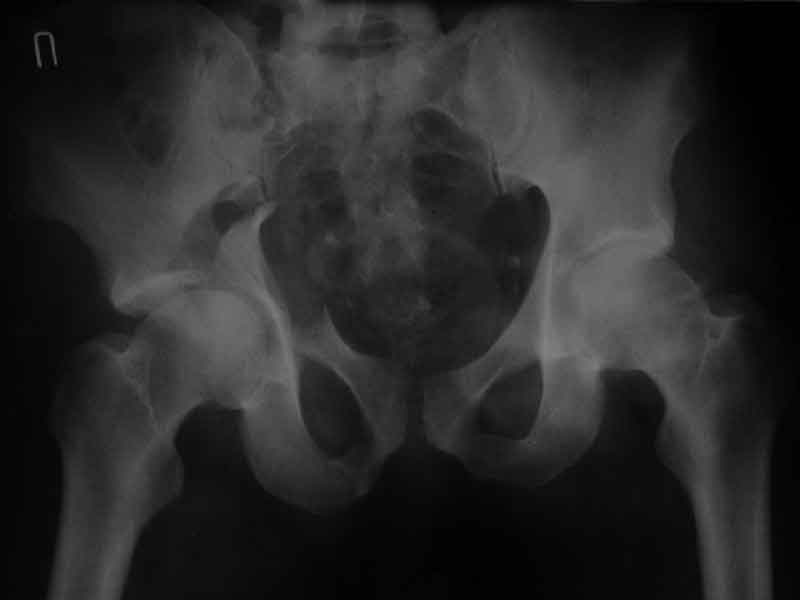

Дополнение, минимальный набор необходимых прекций, необходимых для лечения повреждений вертлужной впадины

Фас. Inlet

Подвздошная Запирательная